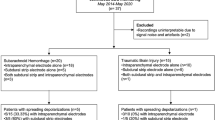

All patients were under sedation with propofol or a combination of propofol and midazolam, with 27 of 32 (84.3%) showing a BS pattern on the scalp EEG and 31 (96.8%) showing a BS pattern in the dEEG at some moment during the cEEGm. In 21 of 32 (65.6%) study participants, highly epileptiform dEEG patterns, including ESzs/ECSzs (11), ESE/ECSE (7), RPPs (17), and SIRPIDs (17), were observed (Fig. 1 and Supplementary Table 2). Seventeen patients (53.1%) had an RPP in the interictal intracortical recording, and 20 (62.5%) had an RPP on the scalp EEG. Of note, in four of five study participants with an RPP detected only on the scalp, this activity occurred contralateral to the side where the intracortical electrode was located. In 18 (56.2%) patients, RDA was observed in the dEEG, whereas unilateral or bilateral scalp RDA was detected in 25 (78.1%) study participants. Moreover, in 15 (46.8%) cases, we observed significant interhemispheric asymmetry on the scalp EEG. Scalp tGPDs were also seen in 15 patients (46.8%) (Supplementary Figs. 1 and 5).

EEG findings of the 32 patients included in the statistical analysis. Asym: interhemispheric asymmetry; iBS: intracortical burst suppression; iECSz: intracortical electroclinical seizure; iECSE: intracortical electroclinical status epilepticus; iESE: intracortical electrographic status epilepticus; iESz: intracortical electrographic seizure; iIIC: intracortical ictal-interictal continuum; iRDA: intracortical rhythmic delta activity; iRPP: intracortical rhythmic and periodic pattern; iSIRPIDs: intracortical stimulus-induced rhythmic periodic or ictal-appearing discharges; sBS: scalp burst suppression; sECSE: scalp electroclinical status epilepticus; sESE: scalp electrographic status epilepticus; sESz: scalp electrographic seizure; sIIC: scalp ictal-interictal continuum; sRDA: scalp rhythmic delta activity; sRPP: scalp rhythmic and periodic pattern; sSIRPIDs: scalp stimulus-induced rhythmic periodic or ictal-appearing discharges; stGPD: triphasic generalized periodic discharges on scalp; TDW: triphasic delta waves